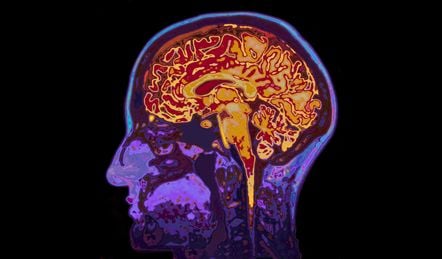

Performing an MRI scan of the brain is a useful diagnosis method for many clinical specialties. But what about mental health?

For some this might be quite surprising. After all, when it comes to the brain, an MRI does more than provide a static image; it measures volume, thickness, neuronal tract density and even activity. In fact, research shows there are structural differences between the brains of patients with diseases like schizophrenia or Alzheimer’s Disease (AD) and the normal brain. One may believe that if you have a mental health problem, surely an MRI could spot it?

When the brain degenerates, memory networks – such as factual, skilled, short-term and long-term – are often affected. With MRI, it is possible to visualise this breakdown in terms of structure and function, and tell some neurodegenerative diseases apart. In AD, for example, damage can be seen relatively early on in the parietal lobe and hippocampus, the region of the brain involved in the formation of new memories. This is why people with AD have problems with short-term memory, yet hold on to past. With Fronto-Temporal Dementia (FTD) the damage is in the frontal lobe and hippocampus.